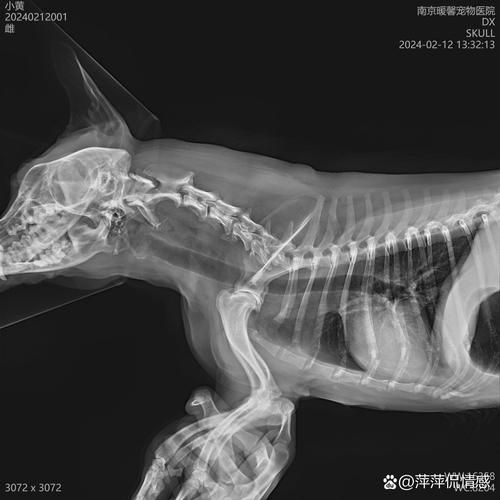

症状识别 当鱼刺卡在狗的喉咙时,会表现出持续性干呕动作,前爪频繁抓挠口部,口腔分泌物明显增多呈拉丝状。部分狗会反复伸舌舔鼻,吞咽时有痛苦表情并发出呜咽声,进食和饮水意愿骤降,严重时可能因食道肿胀导致颈部紧绷僵直。需特别注意有些犬在卡刺初期仍能少量进食,但不能因此排除隐患。

当狗狗被鱼刺卡住时,它们可能会出现干呕、流口水、吞咽困难,咳嗽时会伸长脖子,并用前爪抓嘴。此外,狗狗可能会失去食欲,精神状态也会变差。在严重的情况下,狗狗可能会出现便血或呕吐带血的情况。如果鱼刺卡在喉咙表层,可以用镊子将其取出。但如果鱼刺卡得较深,比较好送狗狗去医院处理。

〖Two〗、怎么判断狗被鱼刺卡住 如果狗被鱼骨卡住,它会干呕、流口水、吞咽,咳嗽的时候向前伸颈,并用前爪抓挠嘴,食欲不振,精神差,严重的情况下可能会出现便血或呕吐的血液。 当鱼骨在浅喉中时,可以张开狗的嘴,用镊子将鱼骨移开,但如果鱼骨太深,比较好将其送到医院。